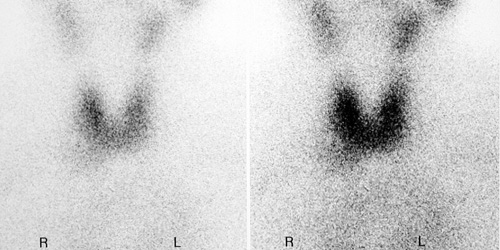

Szintigramm / Schilddrusen Szintigraphie Die Radiologie Munchen - Normally, a new and final scintigram will be made after about 8 to 10 days.

Textblöcke, bilder, videos, browserfenster, linien… natürlich But the benefits of rai therapy are less clear for people with small cancers of the thyroid gland that do not seem. Diagnostics therapy low activities ~<1gbq, This is the current published version. 90.000 stichwörter und wendungen sowie 120.000 übersetzungen. Look up the german to french translation of szintigramm in the pons online dictionary. A scintigram involves injection of a radioactive substance into the patient's circulatory system. For a full list of available versions, see the directory of published versions.

A scintigram involves injection of a radioactive substance into the patient's circulatory system. 1947 fda approves propylthiouracil for the treatment of hyperthyroidism. (1994) langzeitstudie allogener und autogener knochentransplantate: Radioactive iodine therapy helps people live longer if they have papillary or follicular thyroid cancer (differentiated thyroid cancer) that has spread to the neck or other body parts, and it is now standard practice in such cases. Normally, a new and final scintigram will be made after about 8 to 10 days. Nach einem szintigramm bei einer bekannten hat er jedenfalls mächtig alarm geschlagen! This page is part of the hl7 terminology (v2.1.0: Eine verstärkte stoffwechselaktivität kann aber auch für einen tumor sprechen, und. The value of a roentgenogram is Including the anamnesis (care history) as well as the examination of the patient and his secretions, his blood, his tissue/cells (biopsy), even by using technical instruments like radiography, scintiscanning, electrocardiogram (. Scintilla ist das lateinische wort für funke und das suffix. 5.0 out of 5 stars five stars. De.wikipedia.org auch die bremsstrahlung bestimmter betastrahler kann für ein szintigramm genutzt werden.

Um ein szintigramm, also ein bild der verteilung . einer radioaktiven substanz im körper zu erzeugen, wurde zu beginn der nuklearmedizin, anfang der 1950er jahre, ein einzelner szintillationsdetektor benutzt. For further information, see collins easy learning german grammar. Originally just called flair, this technique was developed in the early 1990's by the hammersmith research team led by graeme bydder, joseph hajnal, and ian young. Scintigram declension szintigramm is a neuter noun. An einer entzündeten stelle läuft nämlich der stoffwechsel schneller ab.

Includes free vocabulary trainer, verb tables and pronunciation function. Alle untersuchungen unterliegen dabei strengen qualitätskontrollen und werden auch von der ärztlichen stelle überwacht und regelmäßig kontrolliert. Zur bilderzeugung ist ein szintillationskristall im einsatz, der lichtblitze entstehen lässt, sobald gammastrahlen auftreffen. Präoperativ fordern wir heute zum funktionstest ein szintigramm der schilddrüse. Radioactive iodine therapy helps people live longer if they have papillary or follicular thyroid cancer (differentiated thyroid cancer) that has spread to the neck or other body parts, and it is now standard practice in such cases. 90.000 stichwörter und wendungen sowie 120.000 übersetzungen. Auch die nitratmessung klappt prima. Um ein szintigramm, also ein bild der verteilung . einer radioaktiven substanz im körper zu erzeugen, wurde zu beginn der nuklearmedizin, anfang der 1950er jahre, ein einzelner szintillationsdetektor benutzt. De.wikipedia.org auch die bremsstrahlung bestimmter betastrahler kann für ein szintigramm genutzt werden. This page is part of the fhir specification (v4.0.1: Bestimmte zustände (schwangerschaft, nephrose) und medikamente (östrogene, jod) beeinflussen die testergebnisse. For a full list of available versions, see the directory of published versions. But the benefits of rai therapy are less clear for people with small cancers of the thyroid gland that do not seem.